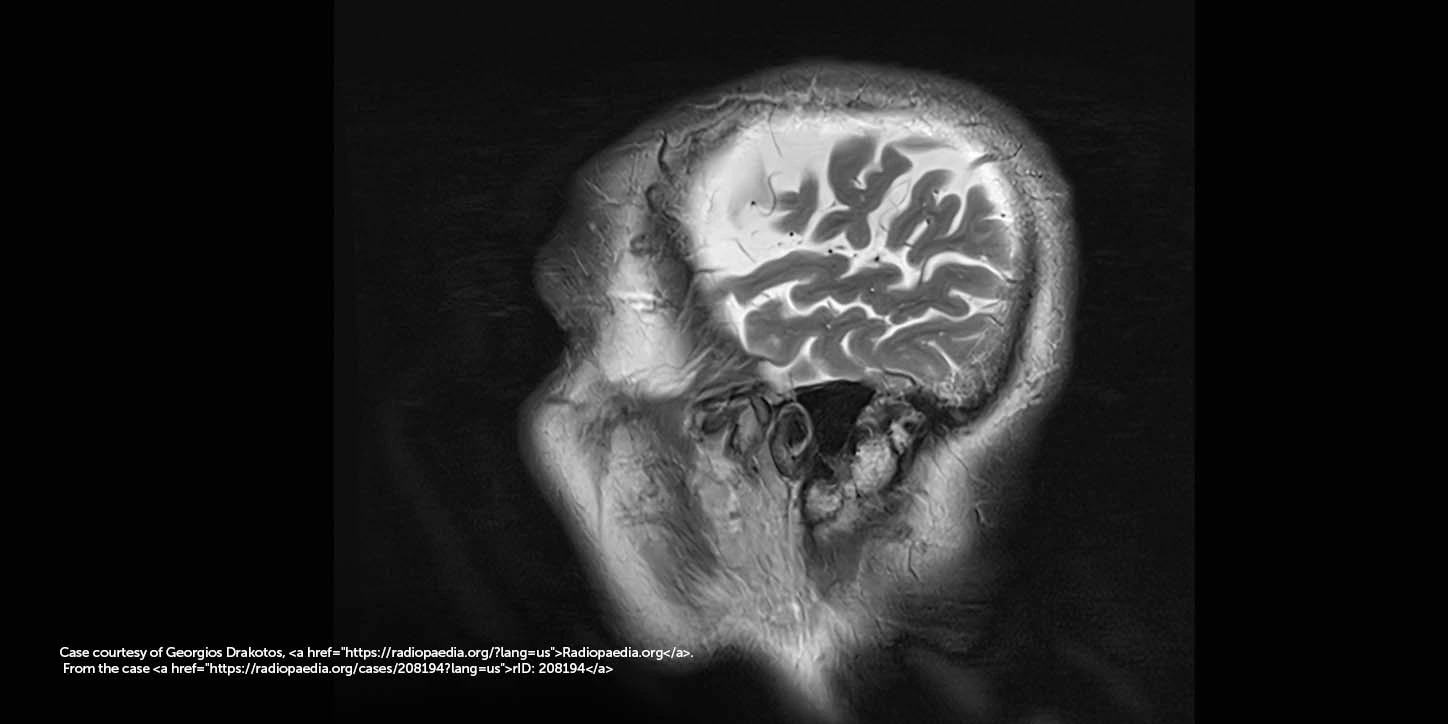

Categoria: Parkinsonismo

O que são os parkinsonismos atípicos? Quando falamos em Doença de Parkinson, logo pensamos em tremor, rigidez e […]

O que é a Degeneração Corticobasal? A Degeneração Corticobasal (DCB) é uma doença neurodegenerativa rara que faz parte […]

O que é a MSA? A Atrofia de Múltiplos Sistemas (MSA) é uma doença neurológica rara, degenerativa e […]

O que é a PSP? A Paralisia Supranuclear Progressiva (PSP) é uma doença neurodegenerativa rara, mas considerada o […]